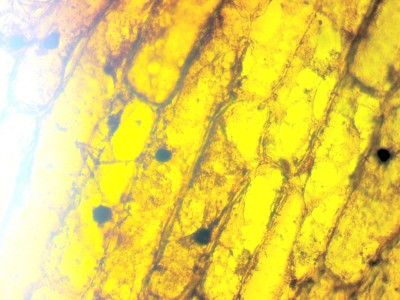

2) Работа с "живым мазком" оказалась весьма проблематичной. Навестись на искомый объект размером около 10-20 микрометров фактически невозможно - он всегде не в фокусе, даже если полностью статичен. Вот пример максимальной резкости, которой мне удалось добиться (рабочее увеличение 400x, без обработки):

Вопросы по работе с камерой 11 Январь 2015 21:08 первое

Остается только догадываться, что из снятого - кристаллы уратов, что - гранулы крахмала, а что - интересующие меня цисты паразитов, благо вариативность размеров и форма у них одинаковая. От двигающихся жгутиконосцев видно вообще только серые размытые тени, которые в статике и заметить-то нельзя. Хотелось картинку примерно такого качества (мазок аналогичный моему и при том же увеличении, но к сожалению не знаю, чем снимали). Мне стоит посмотреть в сторону более дорогой камеры / озаботиться адаптером к своему Canon EOS, или я допускаю какие-то ошибки при работе? Или же проблема вообще в оптике самого микроскопа, и нужны объективы получше для более четкого результата?

2) Работа с "живым мазком" оказалась весьма проблематичной. Навестись на искомый объект размером около 10-20 микрометров фактически невозможно - он всегде не в фокусе, даже если полностью статичен. Вот пример максимальной резкости, которой мне удалось добиться (рабочее увеличение 400x, без обработки)

Возможно, дело в глубине резкости: шарик 20 мкм и плоский диск 20 мкм – это разные вещи для микроскопа. Какова толщина вашего «живого мазка»? А освещение – лампа накаливания, или светодиод? Если лампа накаливания, то должен быть в камере ИК-фильтр; он есть? В общем, причин для размытого изображения может быть много

Остается только догадываться, что из снятого - кристаллы уратов, что - гранулы крахмала, а что - интересующие меня цисты паразитов

Для зерен крахмала применяется окрашивание йодом; цисты паразитов тоже контрастируются йодом, но после формалин-эфирной или уксусно-эфирной седиментации (осаждения). Если нужно, могу выслать на вашу почту пару файлов с методиками гельминтоовоскопии в ветеринарии и медицине. Эффективность нативного мазка невелика [/quote]

Я, к сожалению, слабо представляю, как измерить толщину мазка, но интересуют все-таки шарики, а не диски. Готовила по стандартному методу - развести до прозрачности, при которой хорошо просматривается текст на подложенной газете, капнуть, убрать из рабочего поля все видимые остатки кала, накрыть покровным стеклом. То есть крупных частиц, сильно увеличивающих толщину, там не было. Скопления вот этих разномастных круглых неидентифицируемых штук - были, измерить их высоту я вряд ли смогу.

С этими проще - их можно сначала флотировать, а потом еще и среду для контраста подкрасить, как вы сказали. Плюс увеличение такое не нужно, а значит больше глубина резкости. Но в данном случае я там лямблий высматриваю, причем я надеялась еще и трофозоитов увидеть, не только цисты. Они там есть сто процентов, мазок специально брался от птицы с подтвержденным диагнозом.